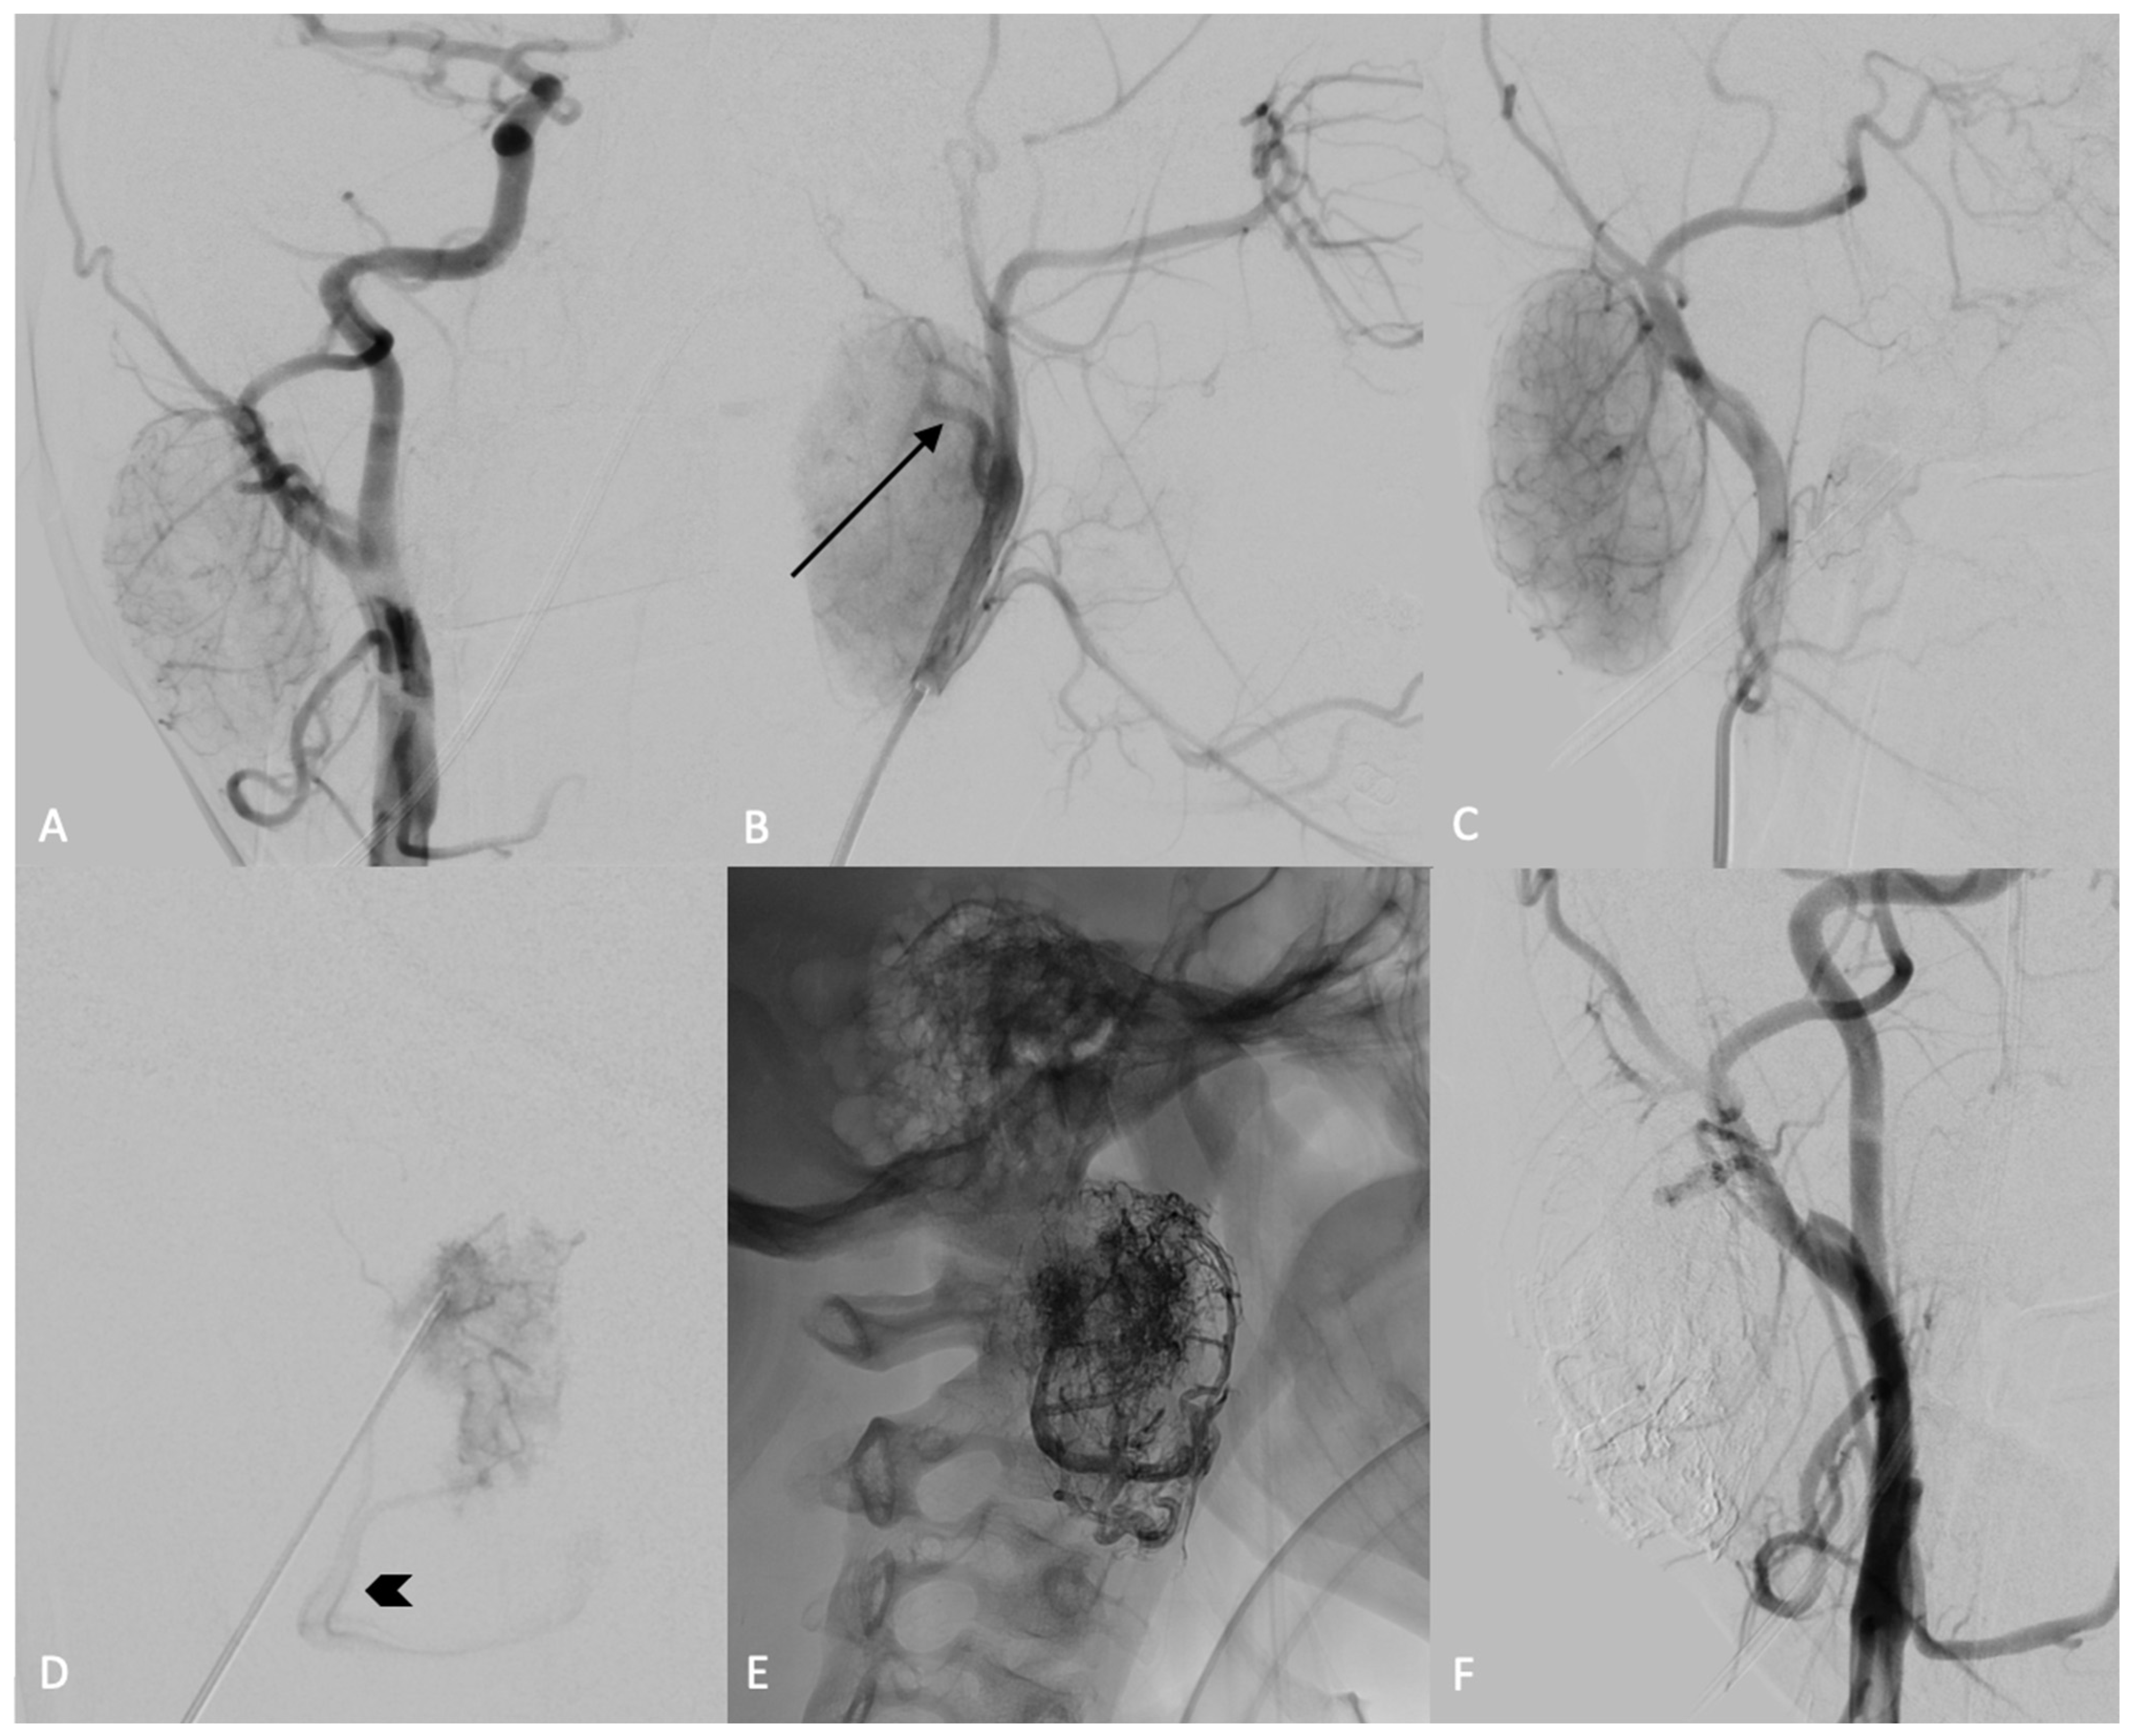

2. Case